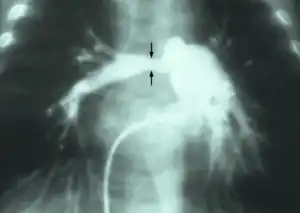

| Stenosis of the right pulmonary artery in a patient which was due to a case of congenital rubella. | |

Stenosis of the pulmonary artery is a condition where the pulmonary artery is subject to an abnormal constriction (or stenosis).[1] Peripheral pulmonary artery stenosis may occur as an isolated event or in association with Alagille syndrome, Berardinelli-Seip congenital lipodystrophy type 1, Costello syndrome, Keutel syndrome, nasodigitoacoustic syndrome (Keipert syndrome), Noonan syndrome or Williams syndrome.